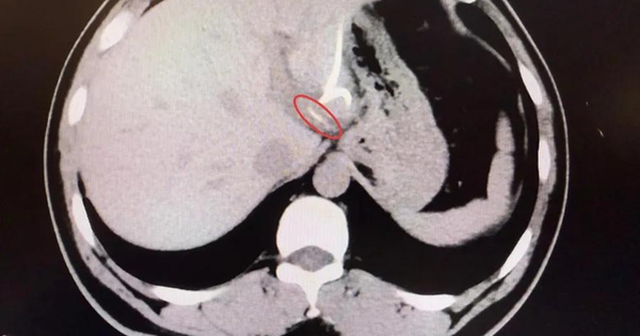

Mãi đến khi chụp CT, các bác sĩ mới phát hiện một vật thể dài, nhọn trong gan trái, gần vùng nối với dạ dày, hình dạng giống hệt… một chiếc xương cá! Hóa ra, chiếc xương này đã xuyên qua thành dạ dày, “chui” thẳng vào gan, gây nhiễm trùng và tạo ổ mủ lớn.

Người đàn ông 37 tuổi suýt mất nửa lá gan vì ăn cá- Ảnh 1.

Sau hơn 3 tiếng đồng hồ, các bác sĩ đã tìm thấy chiếc xương cá dài 3,5cm, sắc nhọn như kim, cắm sâu trong gan trái. Sau ca mổ, anh Lý hồi phục tốt, nhiệt độ cơ thể trở lại bình thường, ổ áp xe dần tiêu biến và quan trọng hơn cả, anh giữ được nguyên vẹn lá gan của mình .